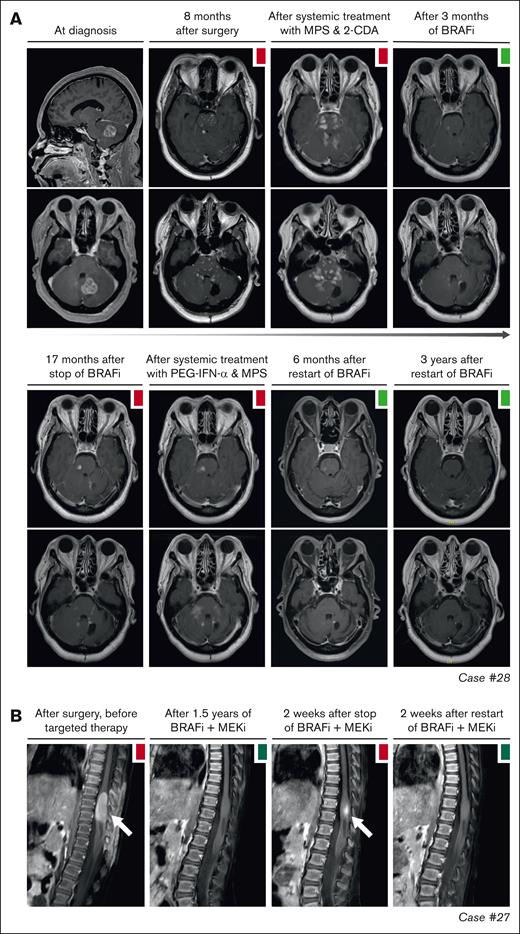

Disease progression after targeted therapy interruption. (A) Sagittal and axial MRI images of case 28, with CNS-AXG showing response of brain lesions to conventional therapies and targeted treatment with vemurafenib. After an initial PR to vemurafenib, targeted treatment was interrupted because of discontinued insurance coverage. Hereafter, brain lesions slowly progressed. Vemurafenib was restarted 3.6 years after interruption and quickly resulted in a decrease of brain lesions, with almost no lesions discernible at last follow-up. (B) Sagittal MRI images of case 27, with CNS-JXG showing relapse of a contrast-enhanced intramedullary spinal cord tumor after targeted therapy interruption. In this young child, treatment with dabrafenib and trametinib was interrupted after 1.6 years of therapy, while in complete radiologic remission. As an exit strategy, trametinib was stopped first, followed by dabrafenib 2 weeks later. MRI after stop of trametinib revealed persistent radiologic CR. However, MRI 2 weeks after stop of dabrafenib revealed recurrence of contrast-enhancement, consistent with a relapse of disease. MRI 2 weeks after restart of dabrafenib and trametinib showed that the radiologic response was recaptured. JXG, juvenile XG; MPS, methylprednisolone.

Objective responses were generally durable, although there were instances of PD in 11 of 27 (41%) patients (Figure 2). In 10 of 11 patients, these instances were related to a dose reduction or therapy interruption. Responses were recaptured in 9 of 10 cases after the dose was increased or therapy was restarted. For example, case 17 with ECD had increased fluorodeoxyglucose uptake in a left acetabular lesion after intermittent dosing of dabrafenib/trametinib (week on/week off; initiated as exit strategy after 3 years of treatment). After returning to continuous therapy, fluorodeoxyglucose uptake in the acetabular lesion decreased again (Figure 3B). Similarly, in case 36 with CNS-RDD (Figure 3C) and cases 27 and 28 with CNS-XG (Figure 4), disease progression was observed on MRI after dose reduction or stop of targeted therapy. In all 3 cases, objective responses were recaptured after dose escalation or restart of therapy (Figure 2). Potential acquired resistance to targeted therapy was only observed in case 16 with ECD, who had progression of a single lung nodule despite adequate intake and dosing of dabrafenib (150 mg twice daily). No biopsy of the nodule was taken. The patient subsequently switched to trametinib, which resulted in a PR at the end of follow-up (Figure 3D).